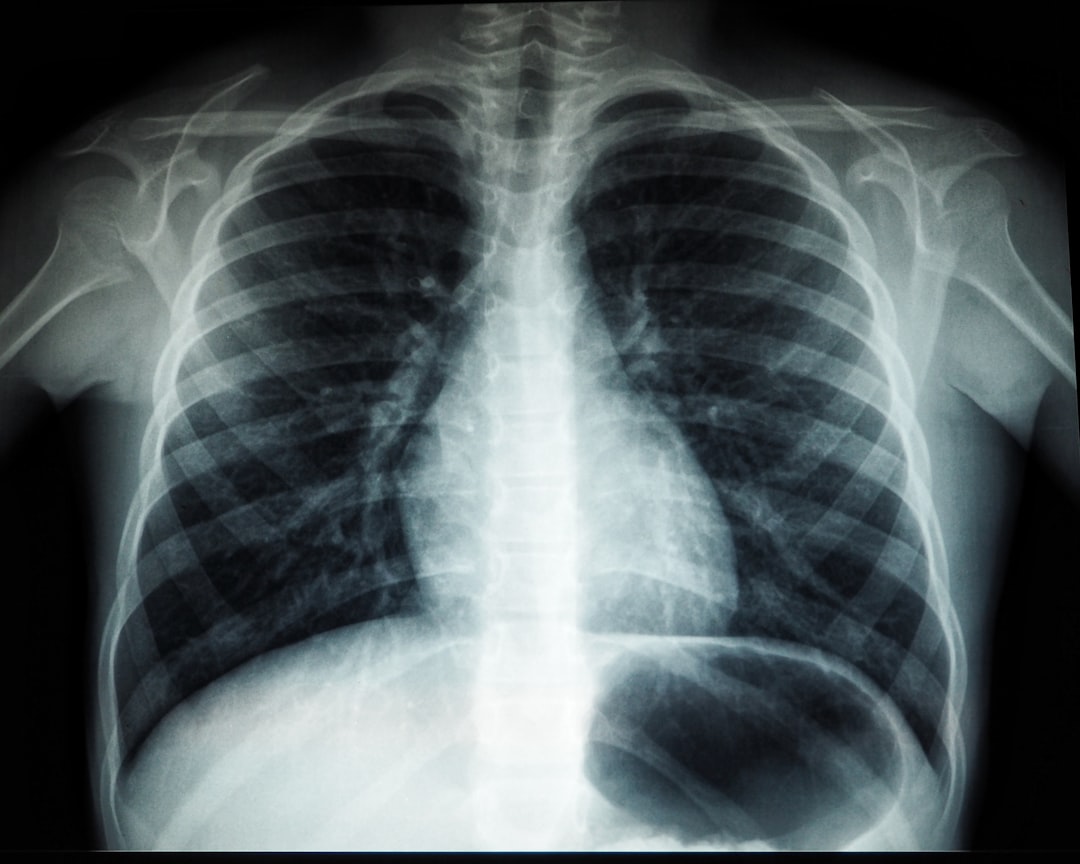

세 번째 방법인 흉부 X-ray 촬영은 폐 결핵이 의심될 때 실시합니다. X-ray를 통해 폐의 상태를 확인하고, 결핵 발병 여부를 판단할 수 있습니다. 검사 후에는 결핵 검사 결과지를 통해 양성 또는 음성 결과를 즉시 받아볼 수 있는 장점이 있습니다. 다양한 방법을 통해 정확한 검사를 받는 것이 필요합니다.

| X-ray 촬영 | 정확한 상태 진단 | 즉시 확인 | 상대적으로 비쌈 |